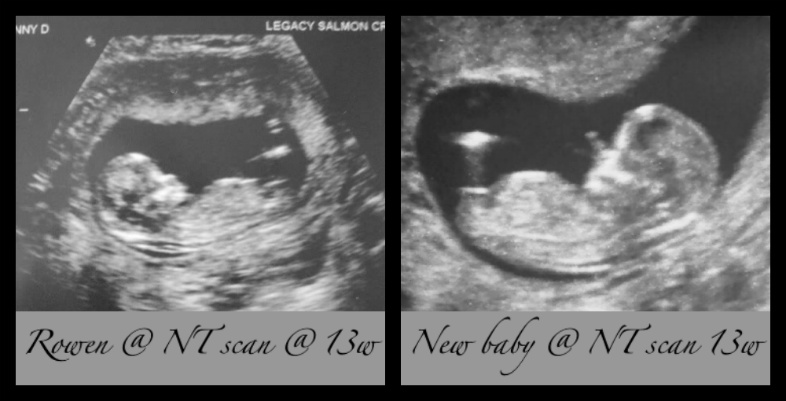

this is my last baby... my first time finding out at delivery.... please give me your gender guesses based on our 13 week US!!Attachment 2868

fyi... here is the 13 week scan from my ds for comparison....Attachment 2869